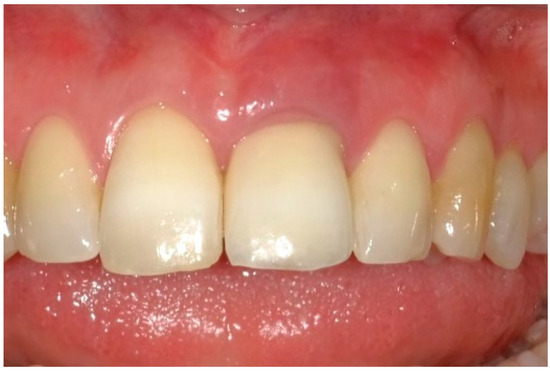

6. Follow-Up

7. Outcomes

| Midfacial mucosa level at Tpre (mm) | 3.0 | 2.0 | 5.0 |

| Midfacial mucosa level at T9 (mm) | 5.0 | 6.0 | 6.0 |

| Midfacial mucosa level at T12 (mm) | 5.0 | 6.0 | 6.0 |

| Mesial papilla | 1 | 1 | 0 | 0 | 2 | 2 |

| Distal papilla | 1 | 1 | 0 | 0 | 2 | 1 |

| Curvature of the facial mucosa | 1 | 1 | 2 | 2 | 1 | 2 |

| Level of the facial mucosa | 0 | 2 | 2 | 1 | 1 | 2 |

| Root convexity/soft tissue color and texture | 0 | 1 | 2 | 2 | 0 | 1 |

| Total | 3 | 6 | 6 | 5 | 6 | 8 |